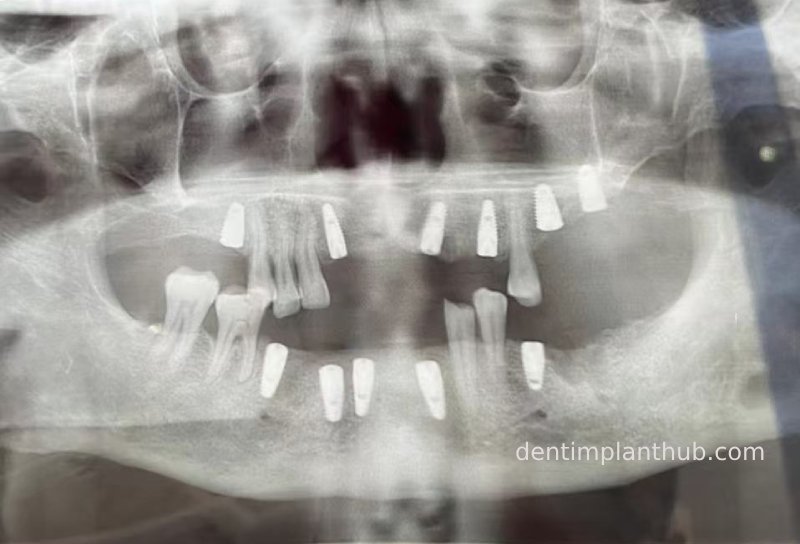

Case 3: Full mouth all-on-6 in a patient with severe periodontal disease